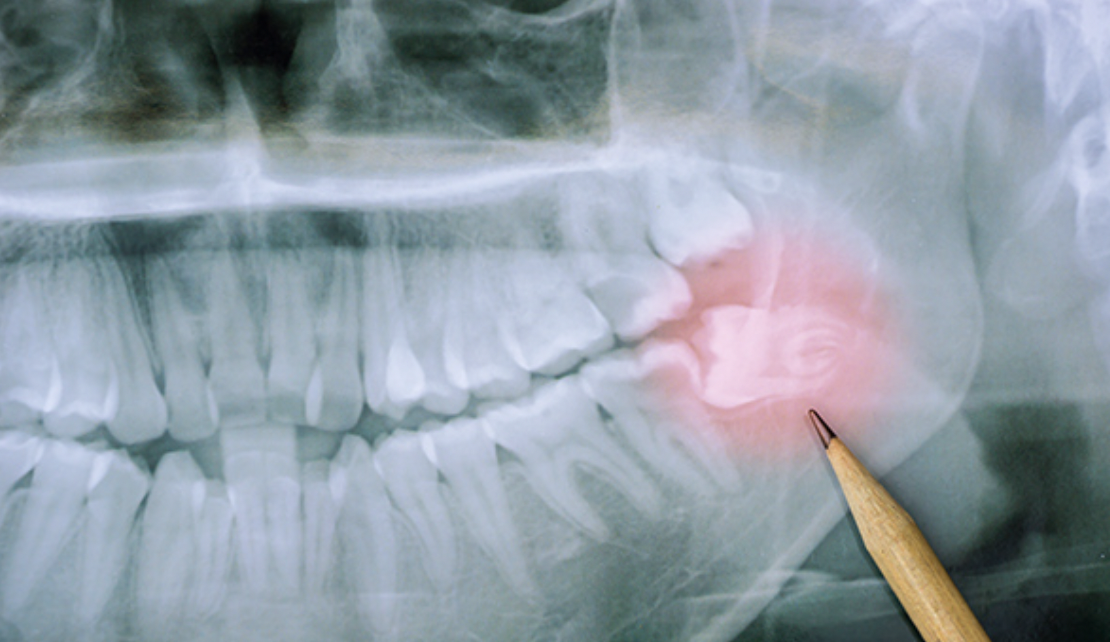

사전 정밀분석

사랑니 발치가 필요한 경우, 치과 의사는 환자의 구강 상태를

정밀하게 분석합니다. 이를 위해 X선이나 CT 스캔을 이용하여

사랑니의 위치, 크기, 각도, 주변 조직과의 관계 등을 확인합니다.

사랑니 발치가 필요한 경우, 치과 의사는 환자의

구강 상태를 정밀하게 분석합니다.

이를 위해 X선이나 CT 스캔을 이용하여 사랑니의 위치,

크기, 각도, 주변 조직과의 관계 등을 확인합니다.